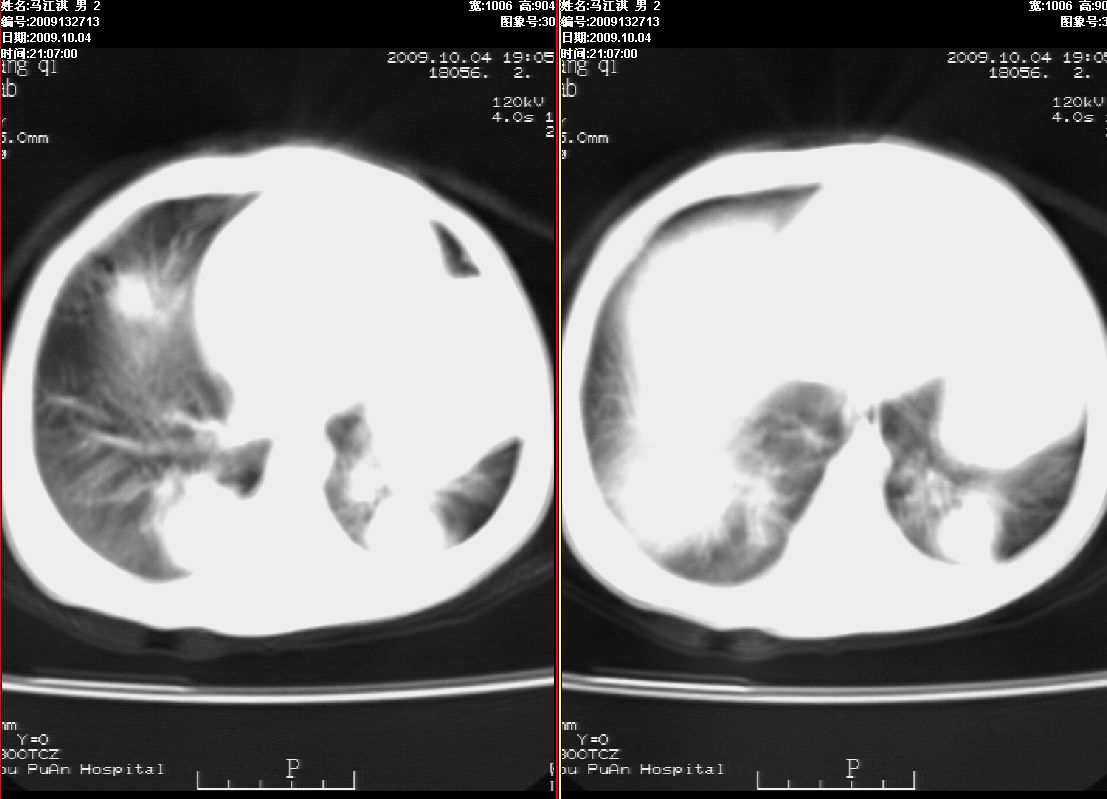

右肾巨大囊性占位病变,其内密度不均,正常肾结构消失,肝脏,肾上腺及肠管等受压移位。双肺内多发大小不等的结节及块状影。考虑右肾母细胞瘤伴双肺多发转移。

肾母细胞瘤(wilms),系儿童最常见的恶性肿瘤,好发于3岁以下儿童,瘤体较大,主要由胚胎性肉瘤样细胞和上皮样细胞构成,临床以腹部肿块;血尿和高血压为主要体征。

ct表现:密度不均匀的大肿块存在;出血和坏死。与神母鉴别点:wilms易向颅脑转移,而神母易往肺转移。

ct表现:密度不均匀的大肿块存在;出血和坏死。与神母鉴别点:wilms易向肺转移。而神母易往颅脑转移.